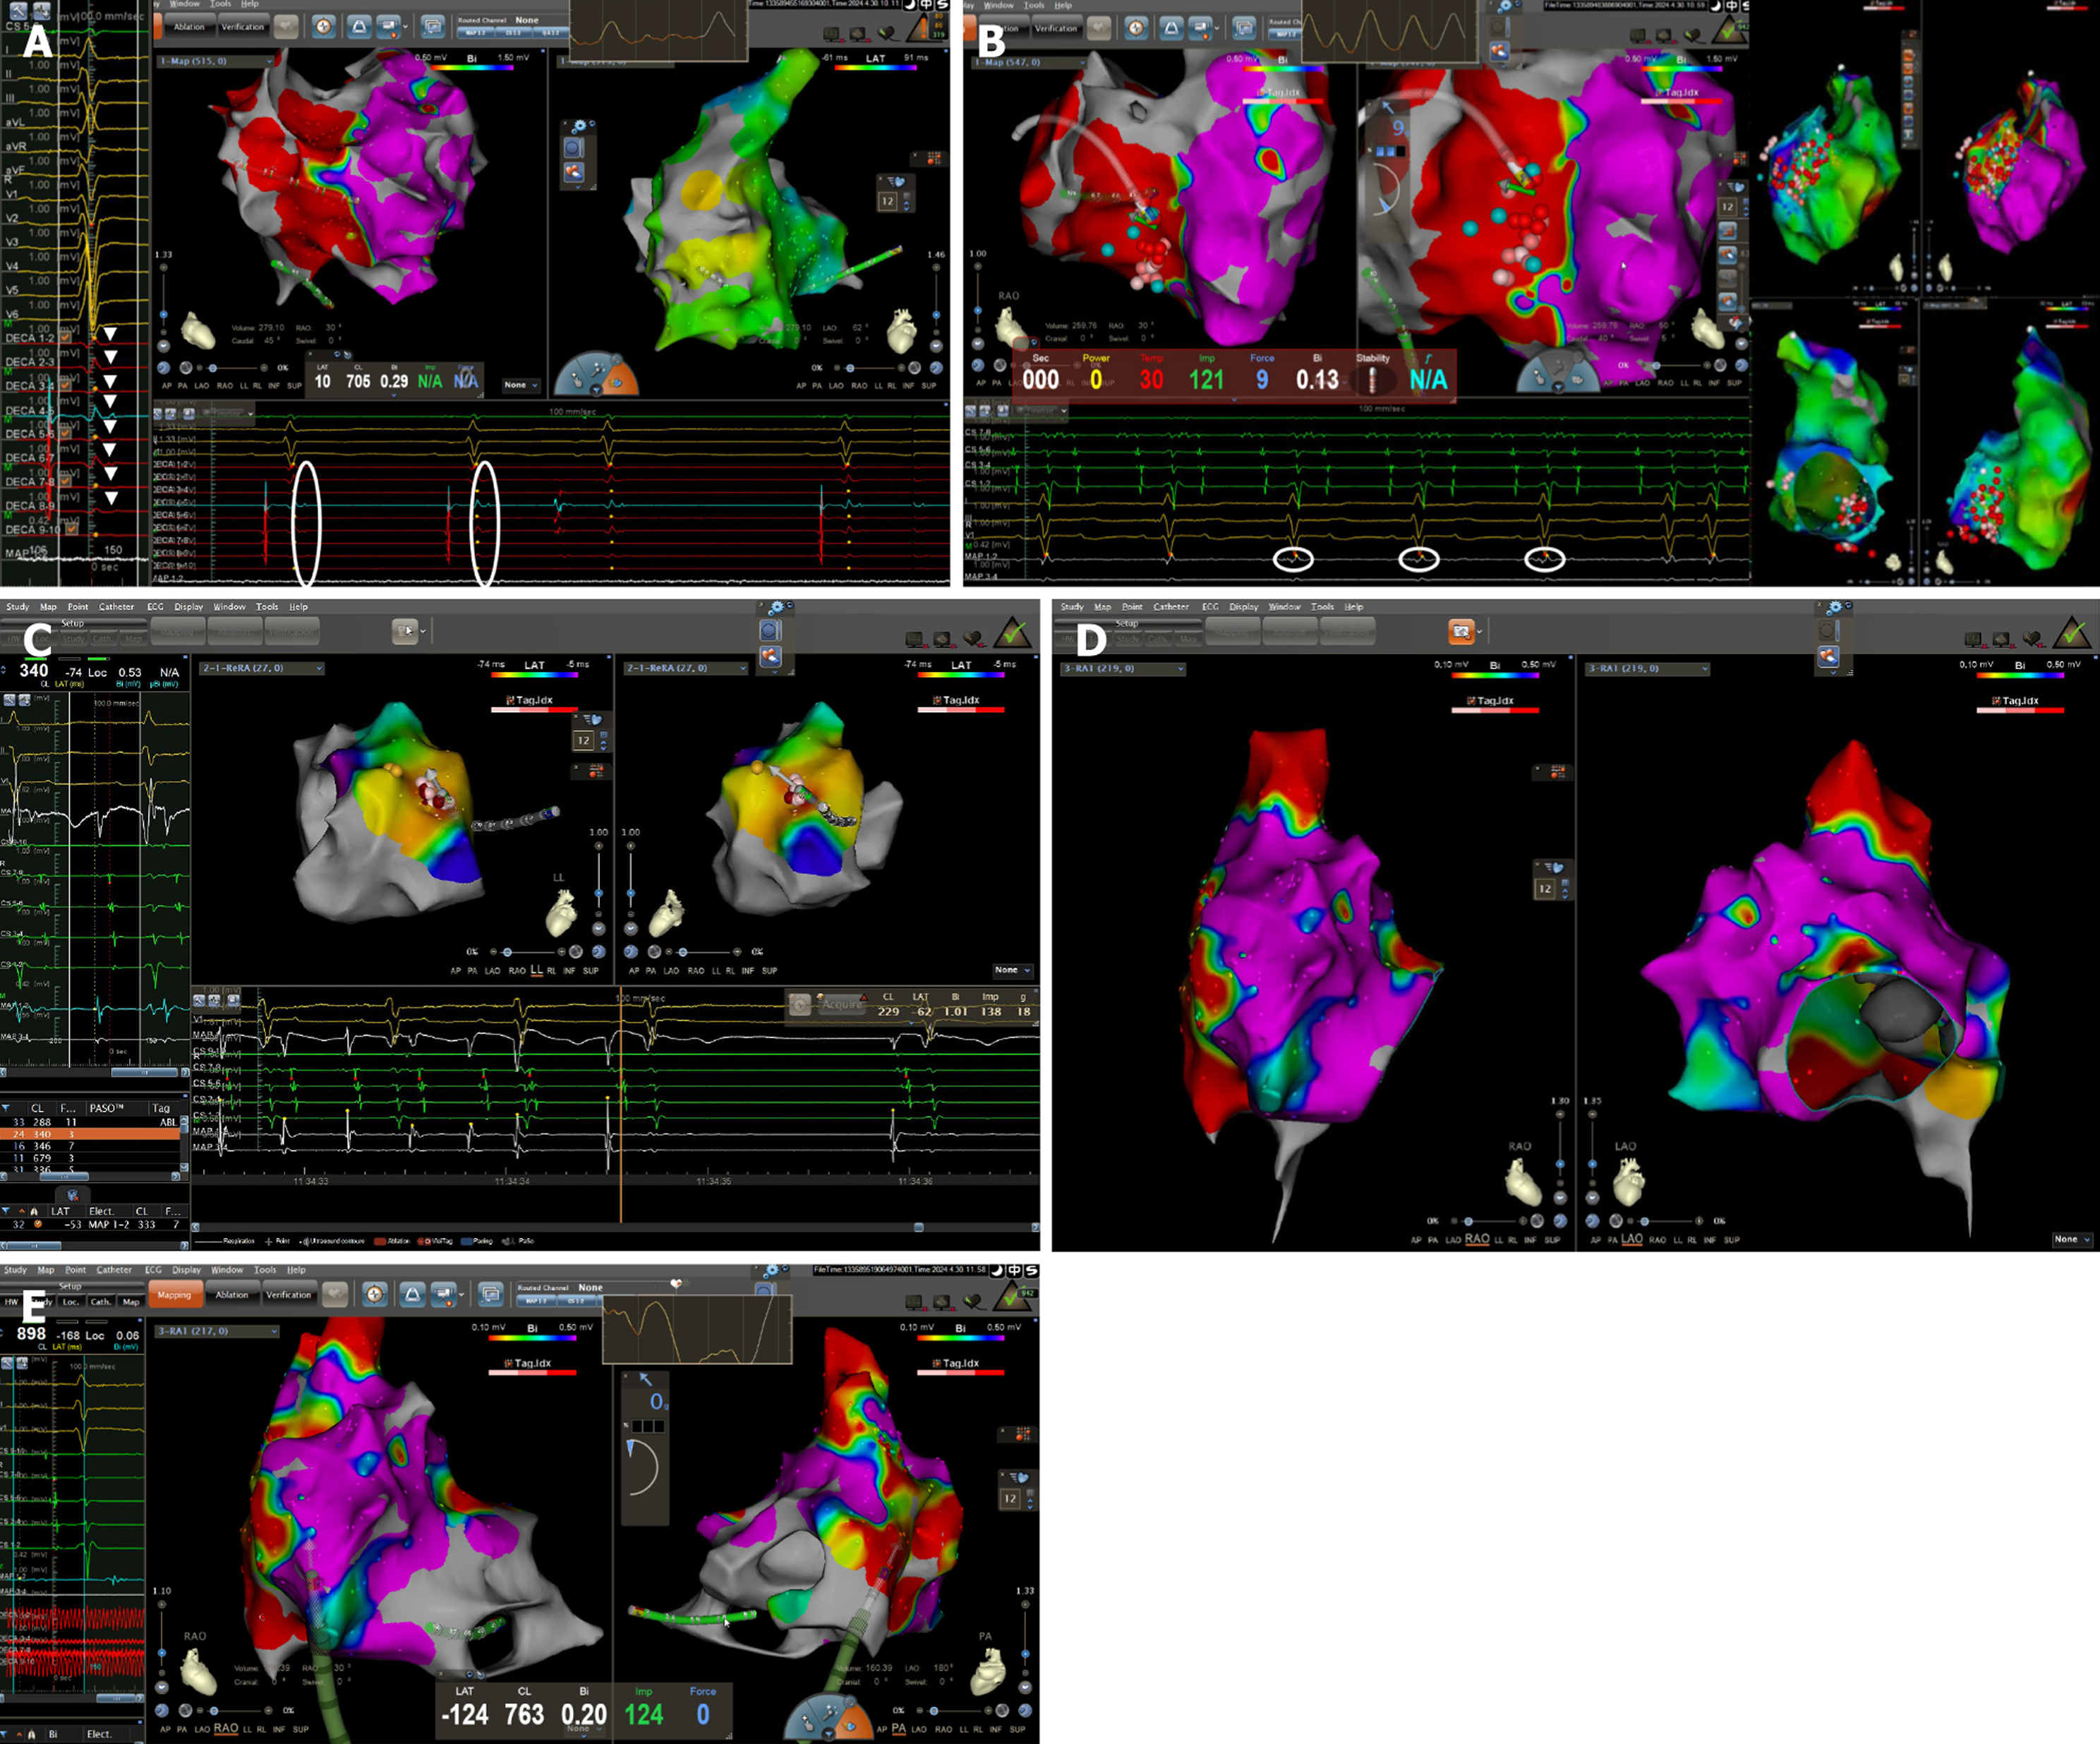

We adopted the method described by Wu et al[1] to induce VT through fast-rate (≥ 250 beats/minute) right ventricular burst stimulation. However, the patient could not tolerate the process, and induction was terminated. Endocardial substrate mapping during sinus rhythm showed extensive scarring and low-voltage areas on the RV free wall (ventricular scar was defined as bipolar electrogram amplitude between 0.5 mV and 1.5 mV during sinus rhythm and dense scar was defined as < 0.5 mV)[2]. Low-frequency, fractionated late potentials were observed along the right ventricular free wall, extending from the tricuspid annulus at the 10 o’clock position down to the low 6 o’clock position (Figure 4A). Concurrently, C-type isolation ring ablation was performed in the low-voltage areas, and homogenization modification was conducted targeting the areas with low-frequency, fractionated late potentials within the isolation rings (Figure 4B).

After confirming bidirectional block and adequate substrate modification, sustained AT was induced during the withdrawal of the mapping catheter. Activation mapping localized the earliest atrial activation site to the para-Hisian region focal AT below the interatrial septum. Mechanical friction around the target site could repeatedly terminate and re-induce AT, long RR pauses and marked sinus bradycardia were observed after AT termination. Electrophysiological study (EPS) showed a sinus node recovery time of 1660 milliseconds. Detailed mapping around the target site identified the earliest atrial activation occurring 37 milliseconds earlier than the surface ECG. Local ablation was performed in sinus rhythm with temperature control of 20 W and a flow rate of 2 mL/minute (500 U/500 mL heparinized saline), and res

Repeated atrial programmed stimulation and burst stimulation, as well as ventricular programmed stimulation, failed to induce the clinical AT or VT. Substrate mapping of the RA revealed extensive low-voltage and scarred areas on the right atrial free wall, posterior wall, and the sinus-node region (atrial dense scar was defined as bipolar electrogram voltage < 0.5 mV during sinus rhythm, and the low-voltage area was defined as abnormal myocardial tissue with voltages < 0.5 mV)[3] (Figure 4D and E). These findings were consistent with the abnormal signal regions seen on pre-procedural cardiac magnetic resonance (CMR) imaging. The post-ablation diagnosis was para-Hisian focal AT and SSS.